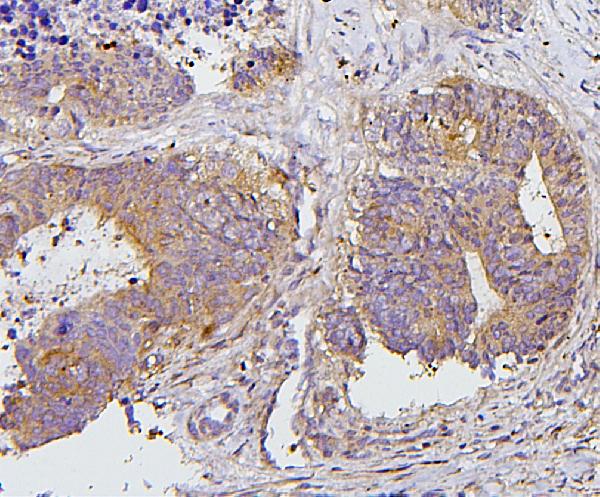

Figure 1. IHC analysis of PRKCD using anti-PRKCD antibody (A00822-1). PRKCD was detected in paraffin-embedded section of human mammary cancer tissues. Heat mediated antigen retrieval was performed in citrate buffer (pH6, epitope retrieval solution) for 20 mins. The tissue section was blocked with 10% goat serum. The tissue section was then incubated with 1microg/ml rabbit anti-PRKCD Antibody (A00822-1) overnight at 4°C. Biotinylated goat anti-rabbit IgG was used as secondary antibody and incubated for 30 minutes at 37°C. The tissue section was developed using Strepavidin-Biotin-Complex (SABC)(Catalog # SA1022) with DAB as the chromogen.